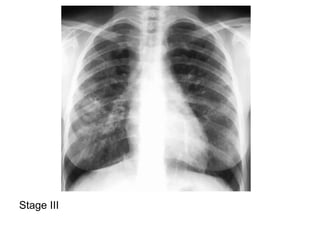

2-Classification :

-May be classified on a chest radiograph into 5

stages :

Stage 0 : normal chest radiograph

Stage I : hilar or mediastinal nodal enlargement

only

Stage II : nodal enlargement and parenchymal

disease

Stage III : parenchymal disease only

Stage IV : end-stage lung (pulmonary fibrosis)

Stage III